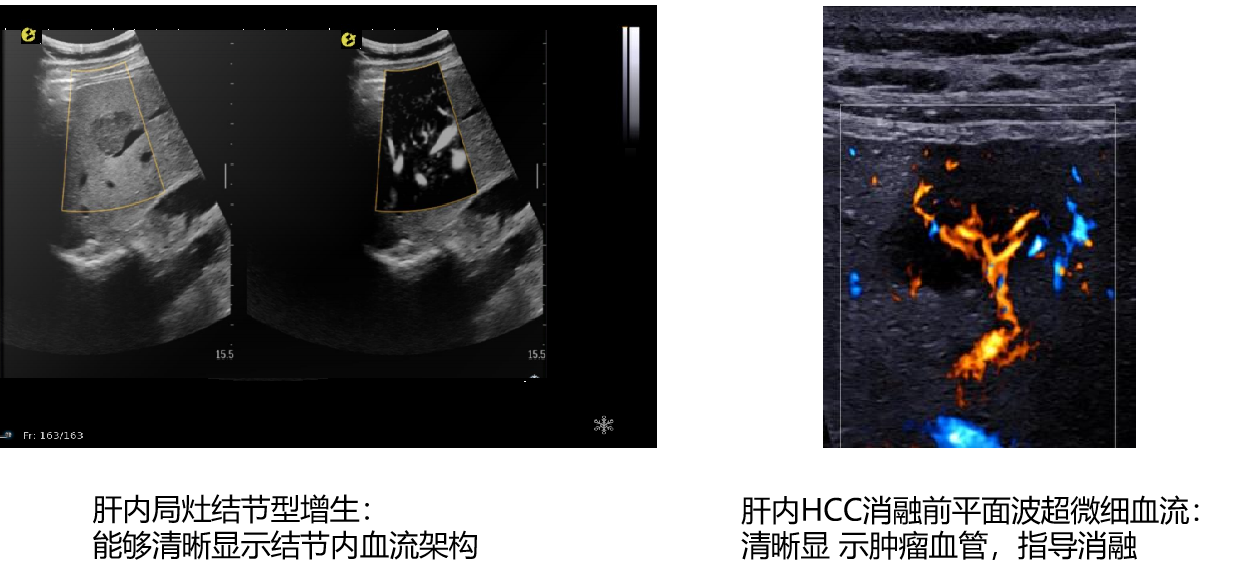

平面波超微细血流显像

能够提供更多真实的组织细小及末梢血管的血流信息,直观的观察组织内部的血管架构及血流形态的情况,提供临床更多有价值的诊断信息。

临床应用:

肿瘤鉴别诊断(肝脏、肾脏、甲状腺、乳腺、  涎腺等)

image.png